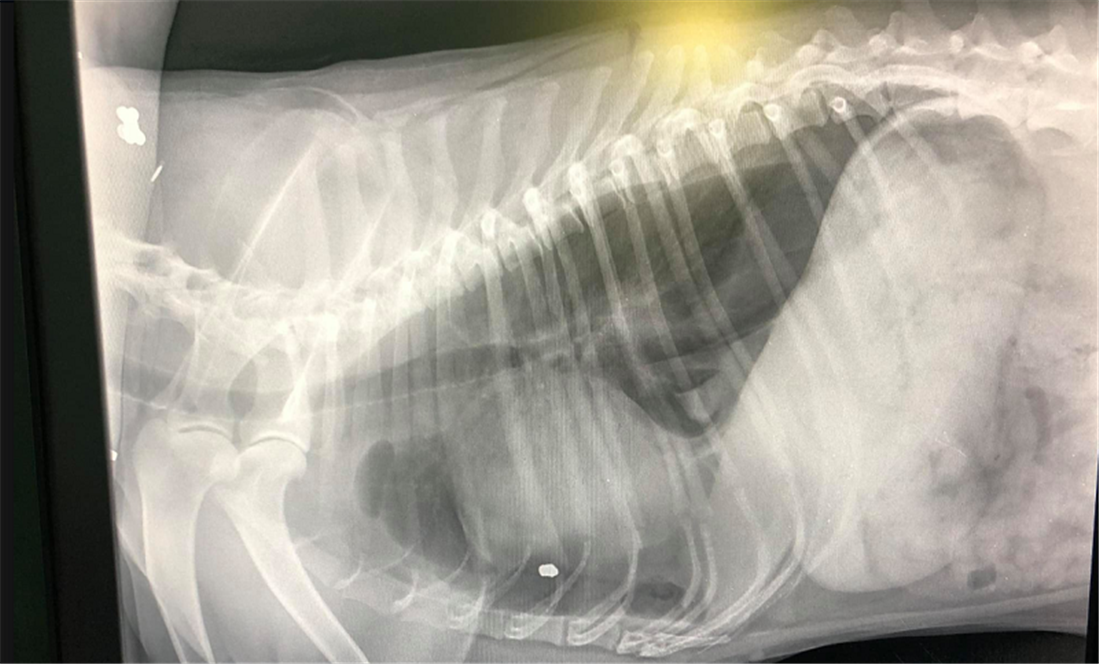

Η βολίδα είχε καρφωθεί στον θώρακα του άτυχου ζώου, ανάμεσα στον πνεύμονα και την καρδιά και αυτή τη στιγμή νοσηλεύεται με οξυγόνο σε κρίσιμη κατάσταση.